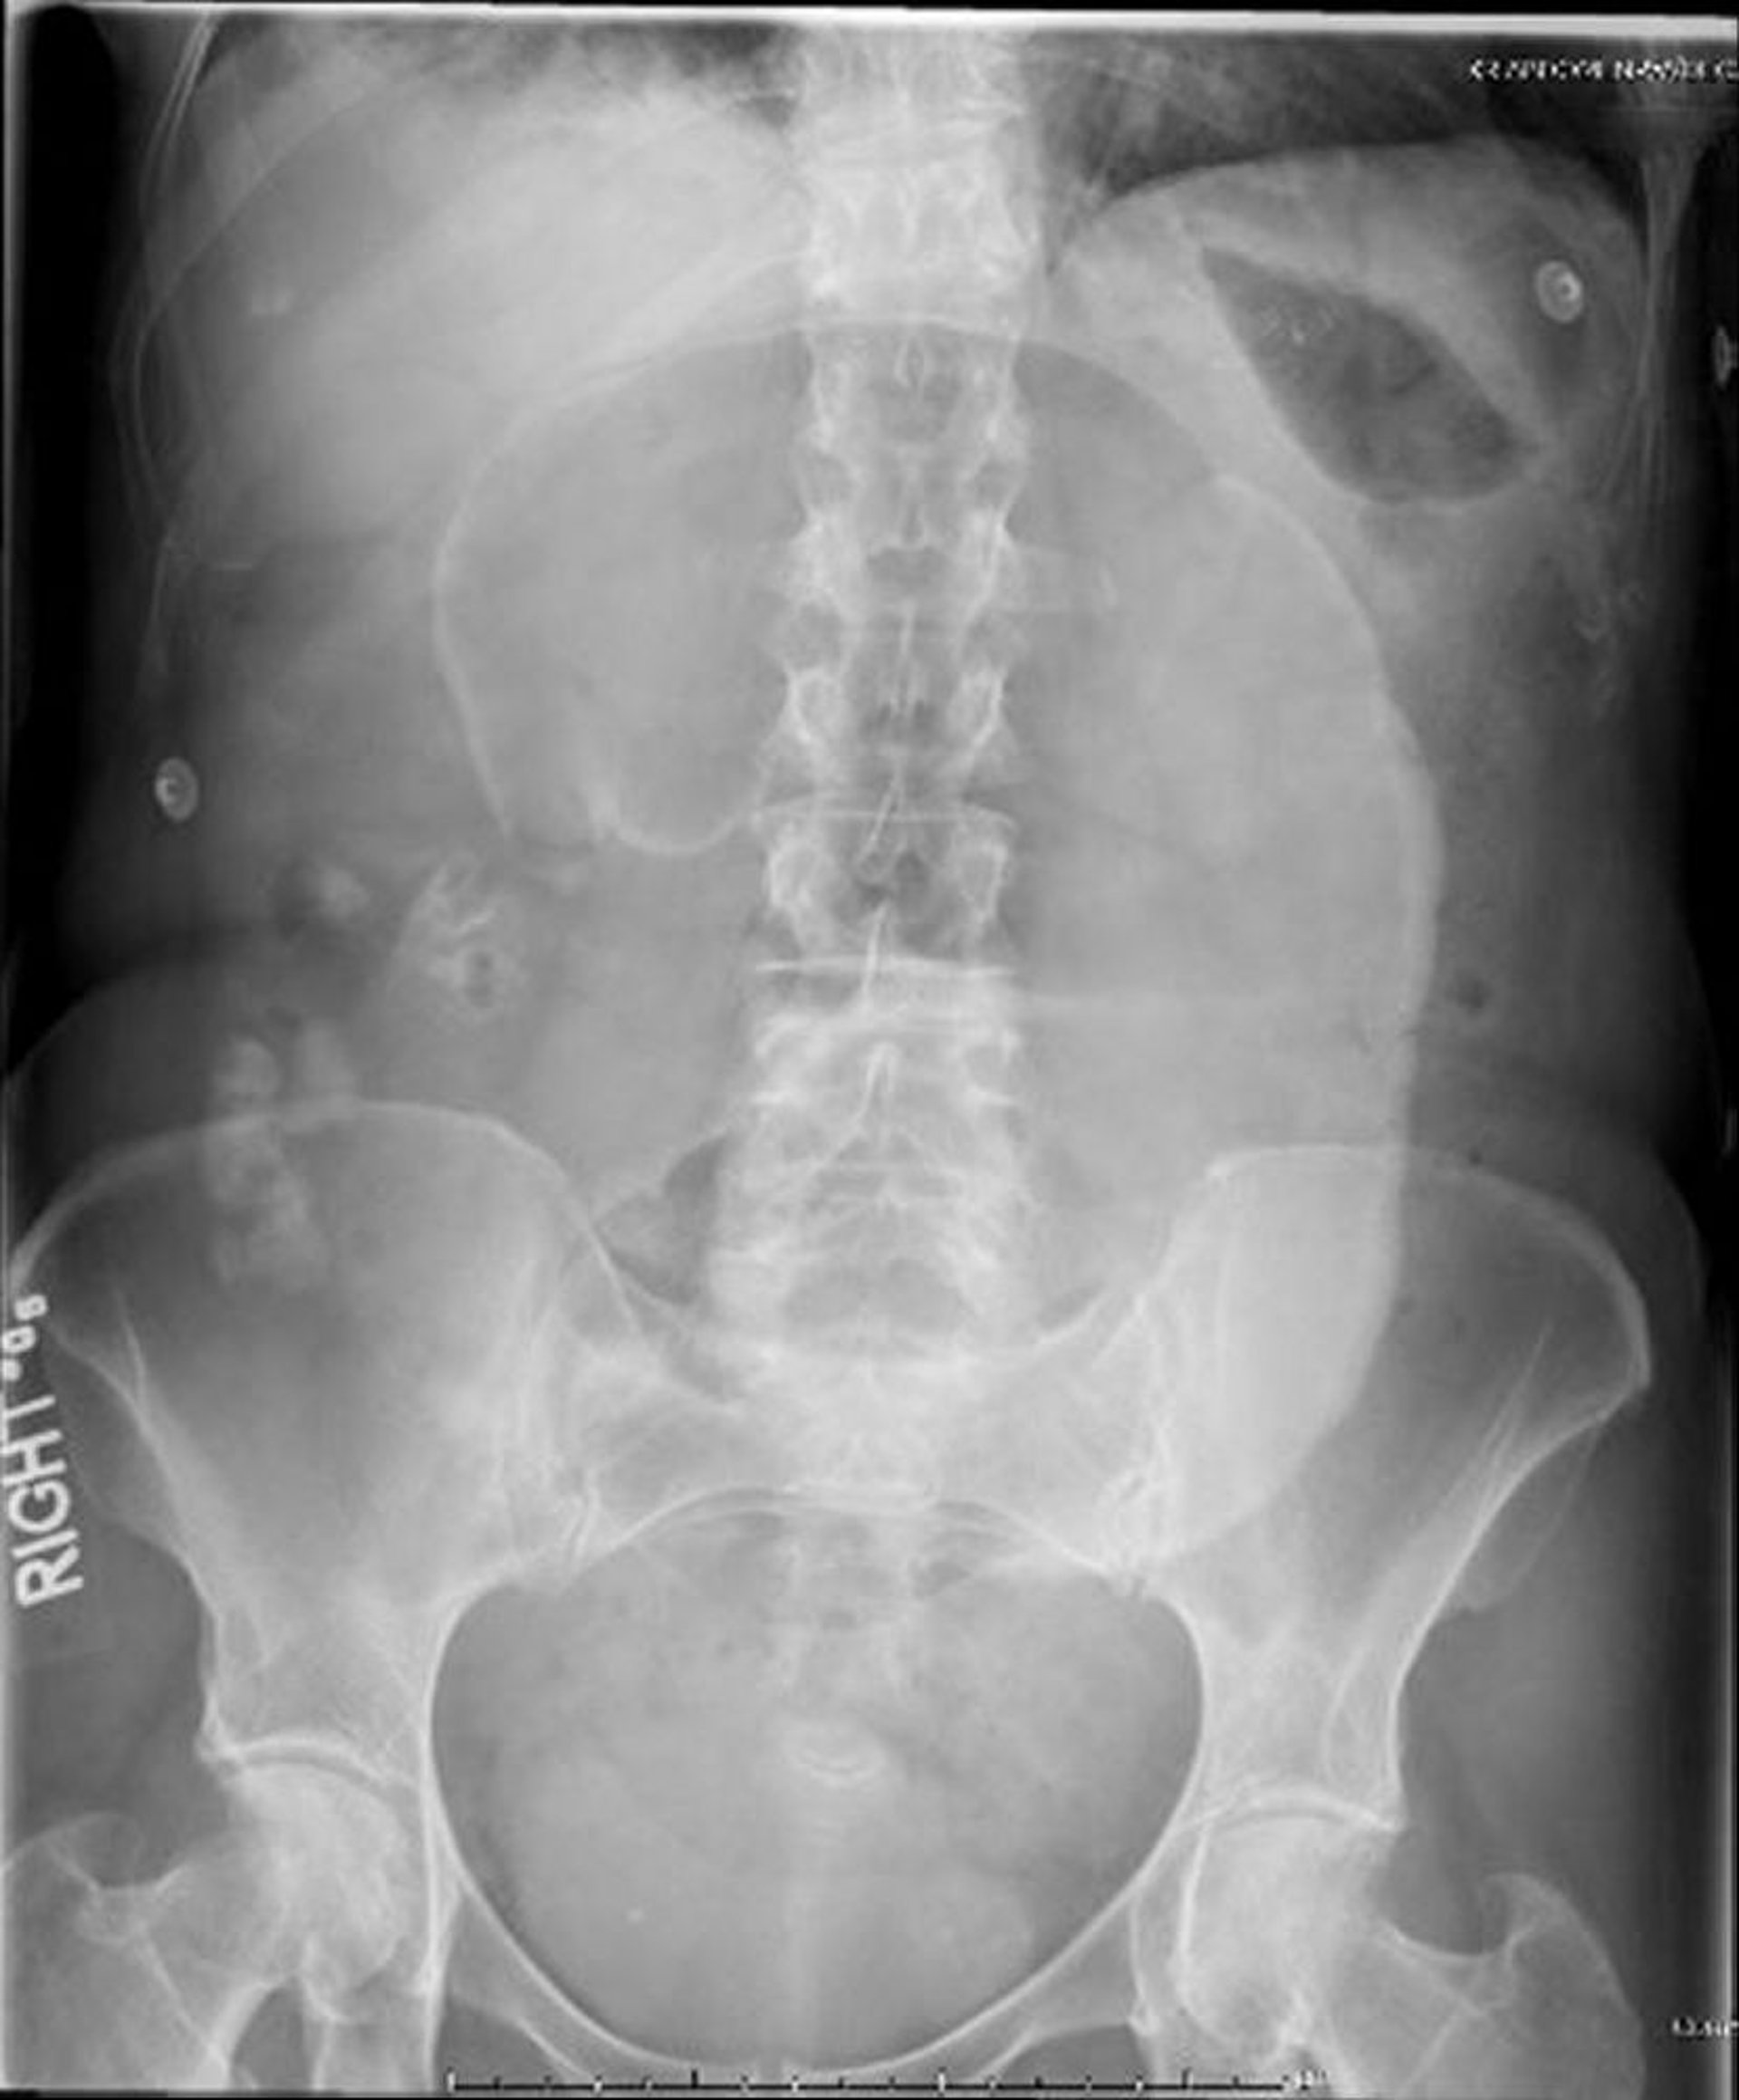

Volvulus du caecum (radio abdominale)

Sur cette radiographie abdominale, le cæcum s'est enroulé autour de son mésentère, provoquant un aspect en 'grain de café' dilaté qui se projette vers l'hypochondre gauche.

Image provided by Parswa Ansari, MD.